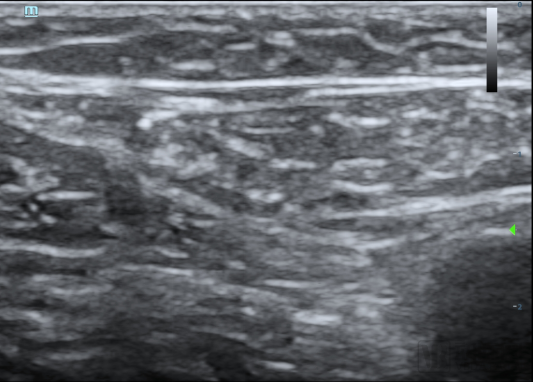

本次臨床試驗的入組患者為63歲男性,其靜脈曲張符合本臨床試驗方案入選入排標(biāo)準(zhǔn)。經(jīng)上海交通大學(xué)醫(yī)學(xué)院附屬第九人民醫(yī)院陸信武主任團隊對患者評估,選擇使用恩盛醫(yī)療自主研發(fā)的VeSeal靜脈閉合系統(tǒng),在超聲影像的引導(dǎo)下采用微創(chuàng)介入的方式將病變血管閉合,整個手術(shù)時間不到半小時。

據(jù)介紹,VeSeal靜脈閉合系統(tǒng)不同于其他臨床研究,VeSeal還配備了輸送導(dǎo)絲及導(dǎo)管鞘管等標(biāo)準(zhǔn)配件,注射導(dǎo)管在超聲下實時可見,鞘管具有標(biāo)尺,手術(shù)過程無需其它配件,方便臨床醫(yī)生快速、便捷、高效的將病變血管閉合。